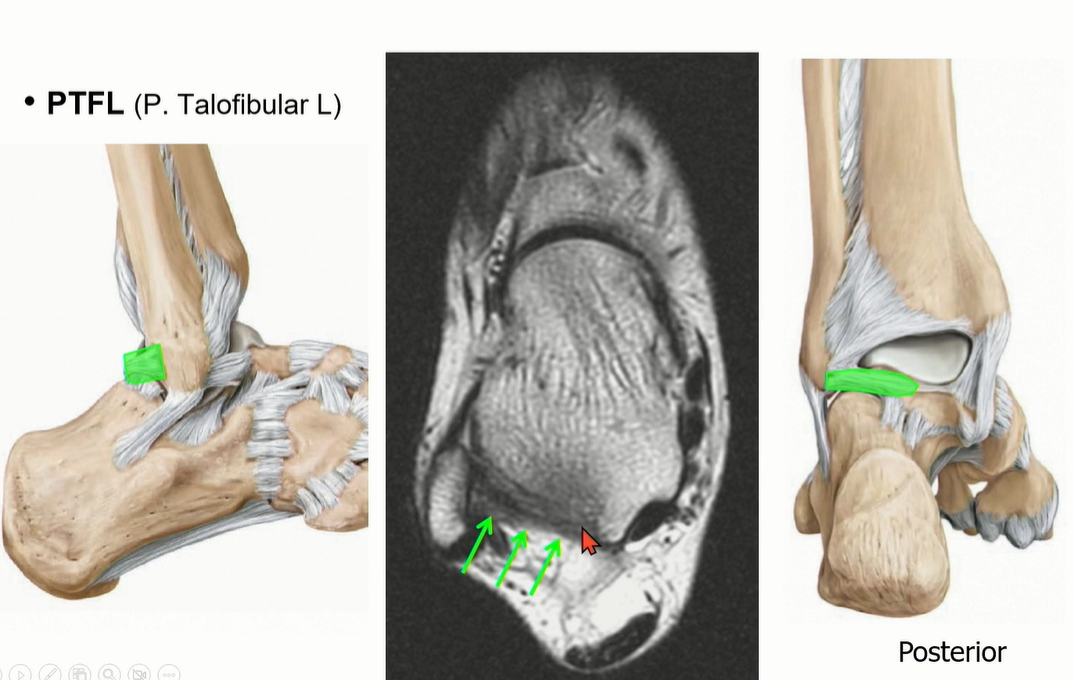

2-3 . PTFL (posterior talofibular ligament)

3가지 중에서 가장 두껍고 튼튼해서 injury가 제일 적다. 정상적인 상태에서도 ligament 내부로 fat portion이 있음.